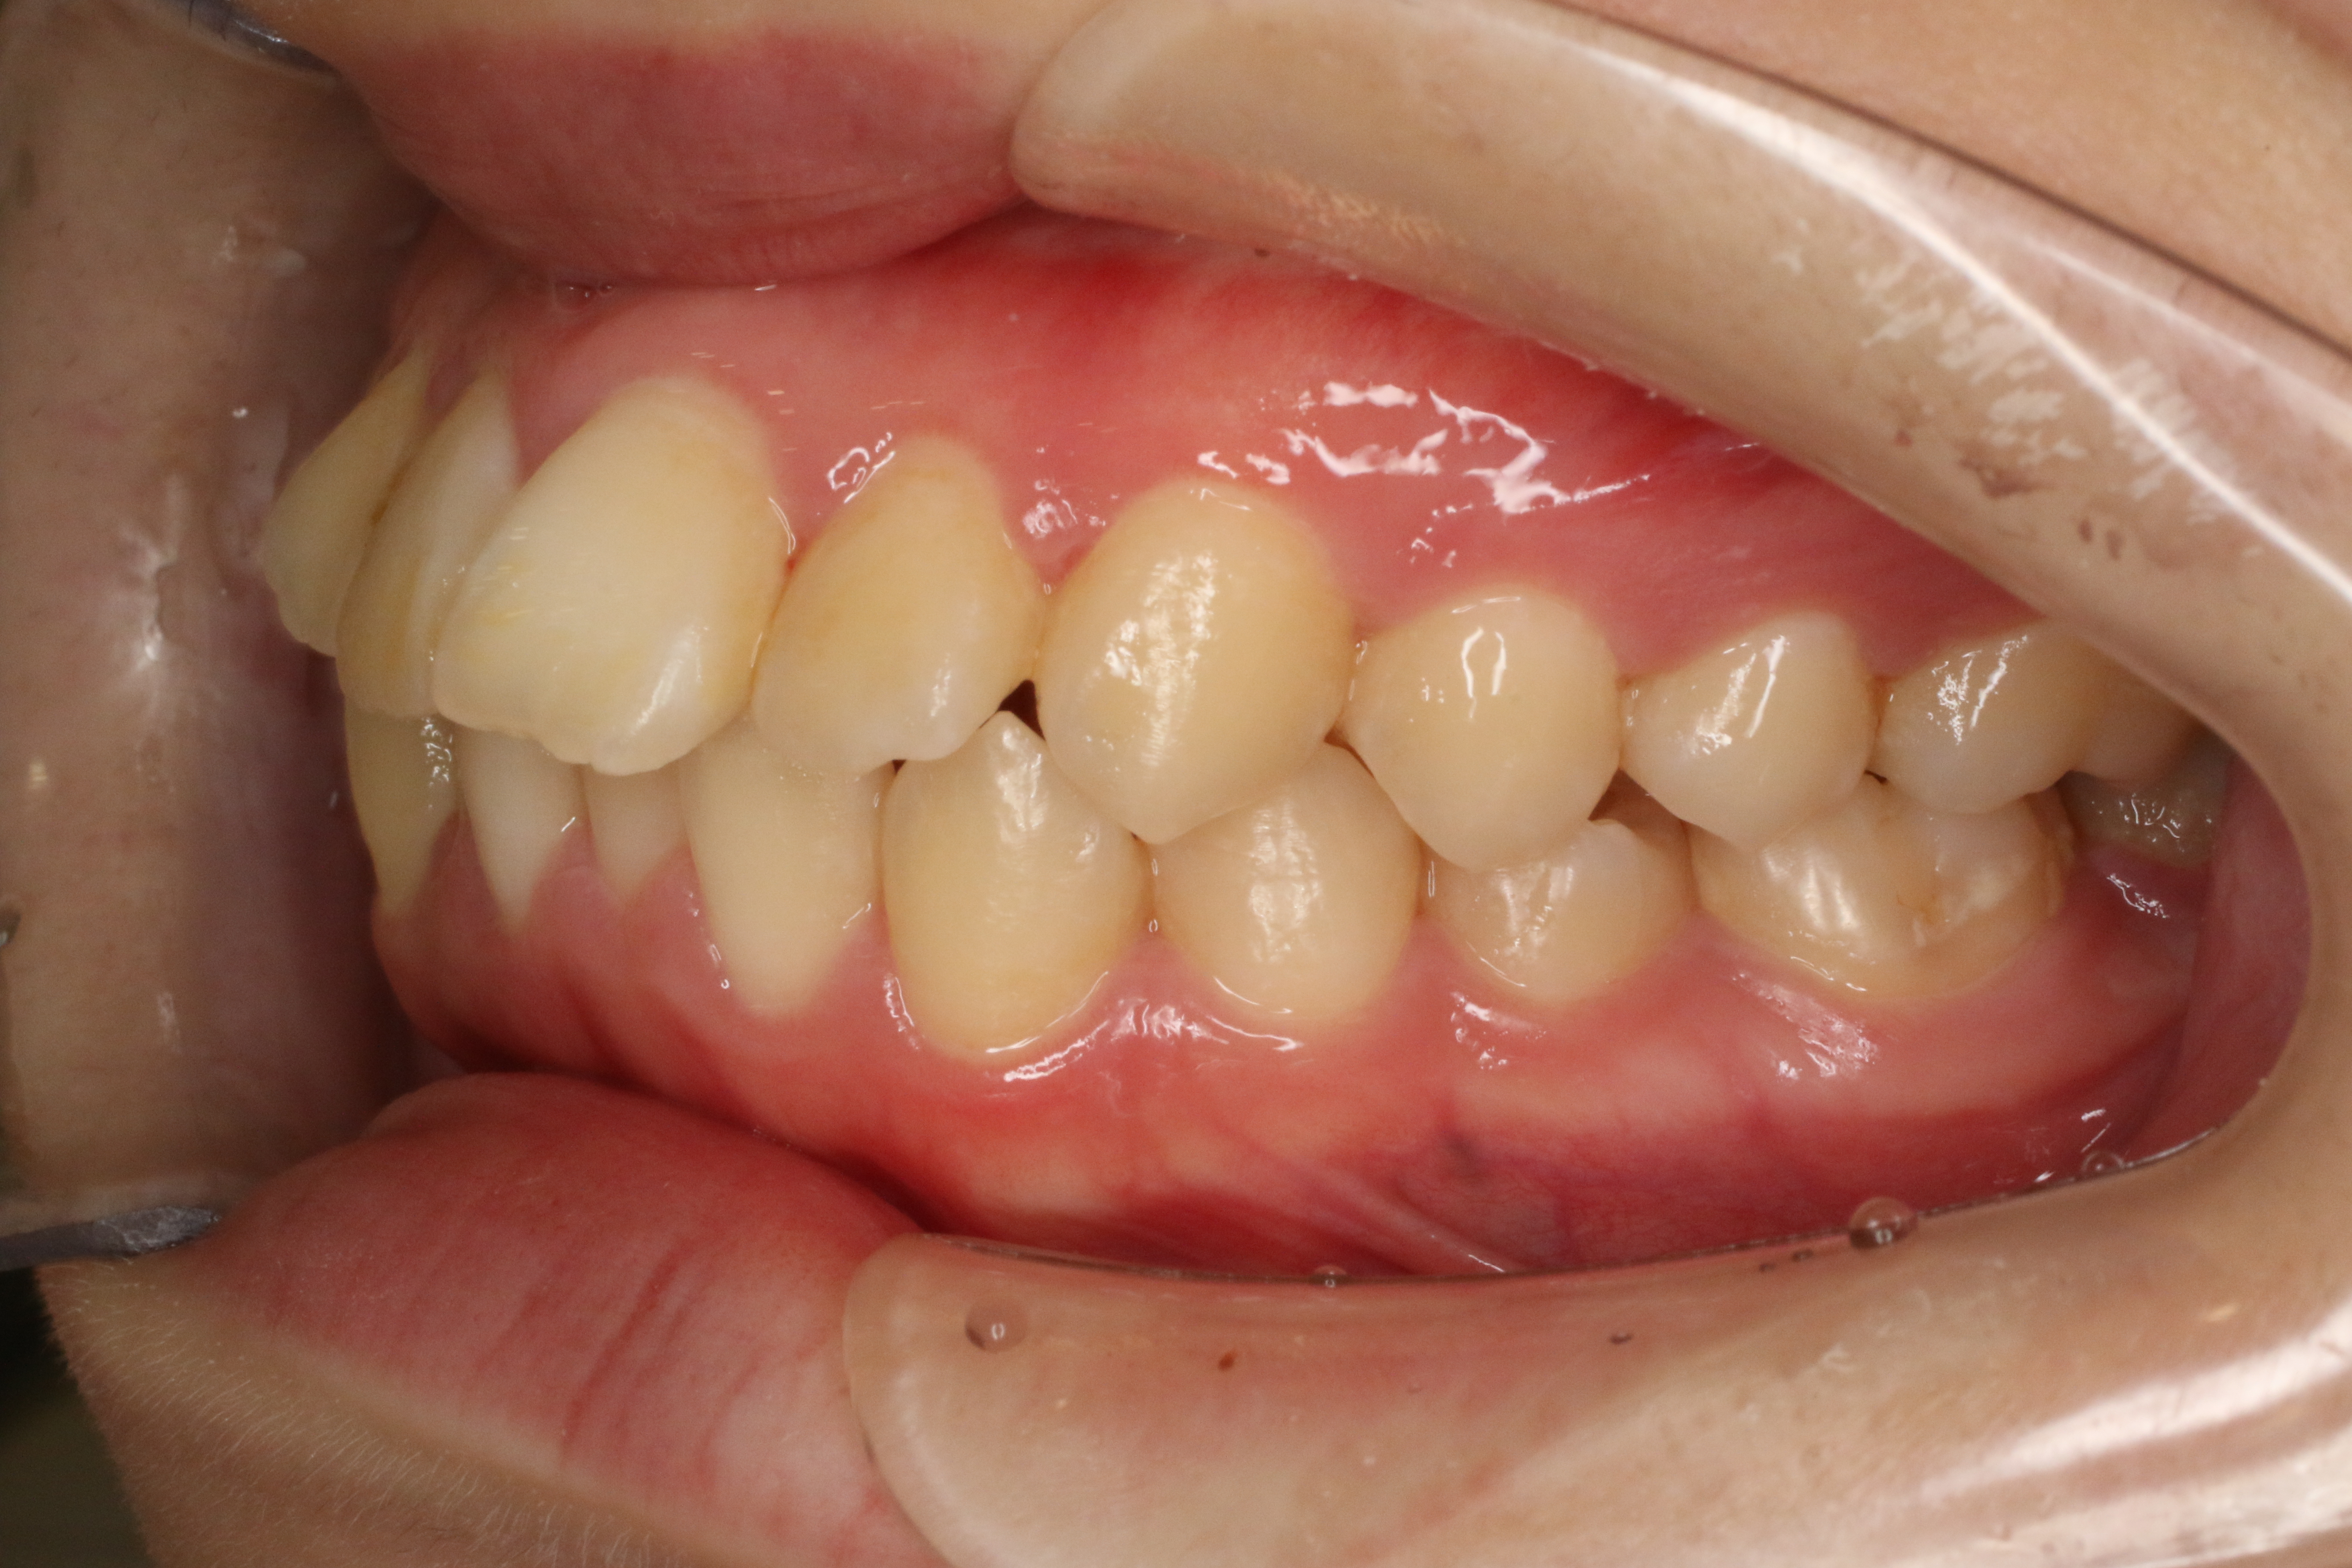

すきっ歯を治したい

年齢層 20代

性別 女性

主訴 【主訴】すきっ歯を治したい 【診断・症状】空隙歯列、1,1正中離開

治療費用 検査・診断:38,500-/裏側矯正治療:1,397,000-(※全て税込)

治療期間 約1年8か月(22回)

抜歯 無(非抜歯)

矯正の装置 裏側矯正(舌側矯正)

副作用、リスク 歯肉退縮,歯根吸収,疼痛,咬合の違和感,装置の違和感,虫歯,歯肉炎